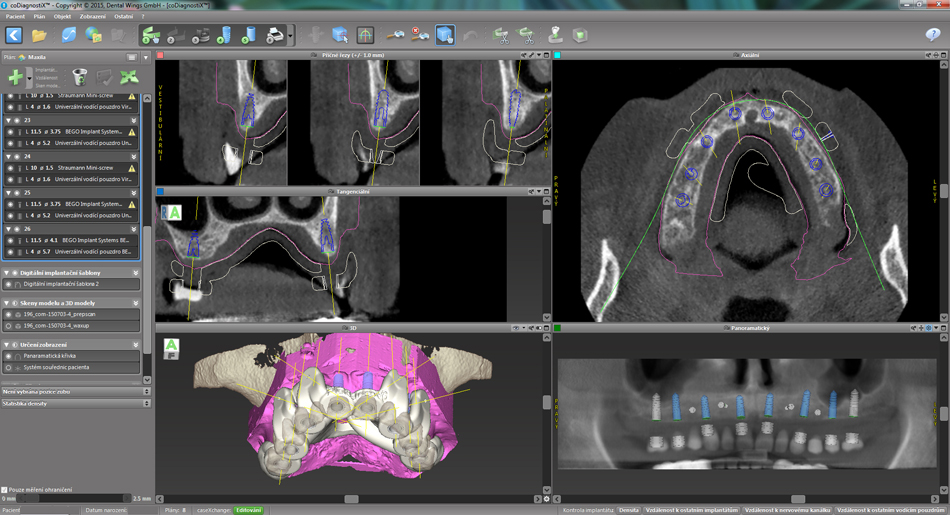

Jedná se o externí plánovací program, spojený se zubní laboratoří a frézovacím centrem, který využívá dat získaných z 3D rentgenu čelisti, otisku zubů a dásně (scanu zubů a dásně) a finálního návrhu protetické náhrady. Tento program umožňuje tříprostorovou počítačovou simulaci při plánování pozic implantátů. Součástí programu je i databáze, ve které mohou být uloženy všechny typy implantátů od všech výrobců, včetně jejich délek, průměrů i tvarů.

Lékař si vytvoří všechny typy zobrazení potřebných pro naplánování – tedy 2D snímky (panoramatický), příčné řezy i 3D model.

Vidí zde i důležité anatomické útvary – čelistní dutinu, průběh nervu atd. Po proměření množství kosti – šířky i výšky vybere z databáze vhodný typ implantátu a umístí ho do požadované lokality. Ihned vidí jeho pozici ve všech 3 rovinách a na všech snímcích i 3D modelu. Může upravovat podle potřeby jeho pozici, sklon atd.

Všechny vybrané a správně umístěné simulované implantáty se ukládají do „počítačové karty“ pacienta s jejich pozicí, délkou, průměrem, typem i sklonem. V programu také lékař navrhuje chirurgické šablony pro řízenou nebo navigovanou implantaci. Lékař i pacient tedy ještě před vlastní operací vidí, jak by mělo ošetření probíhat a vypadat.